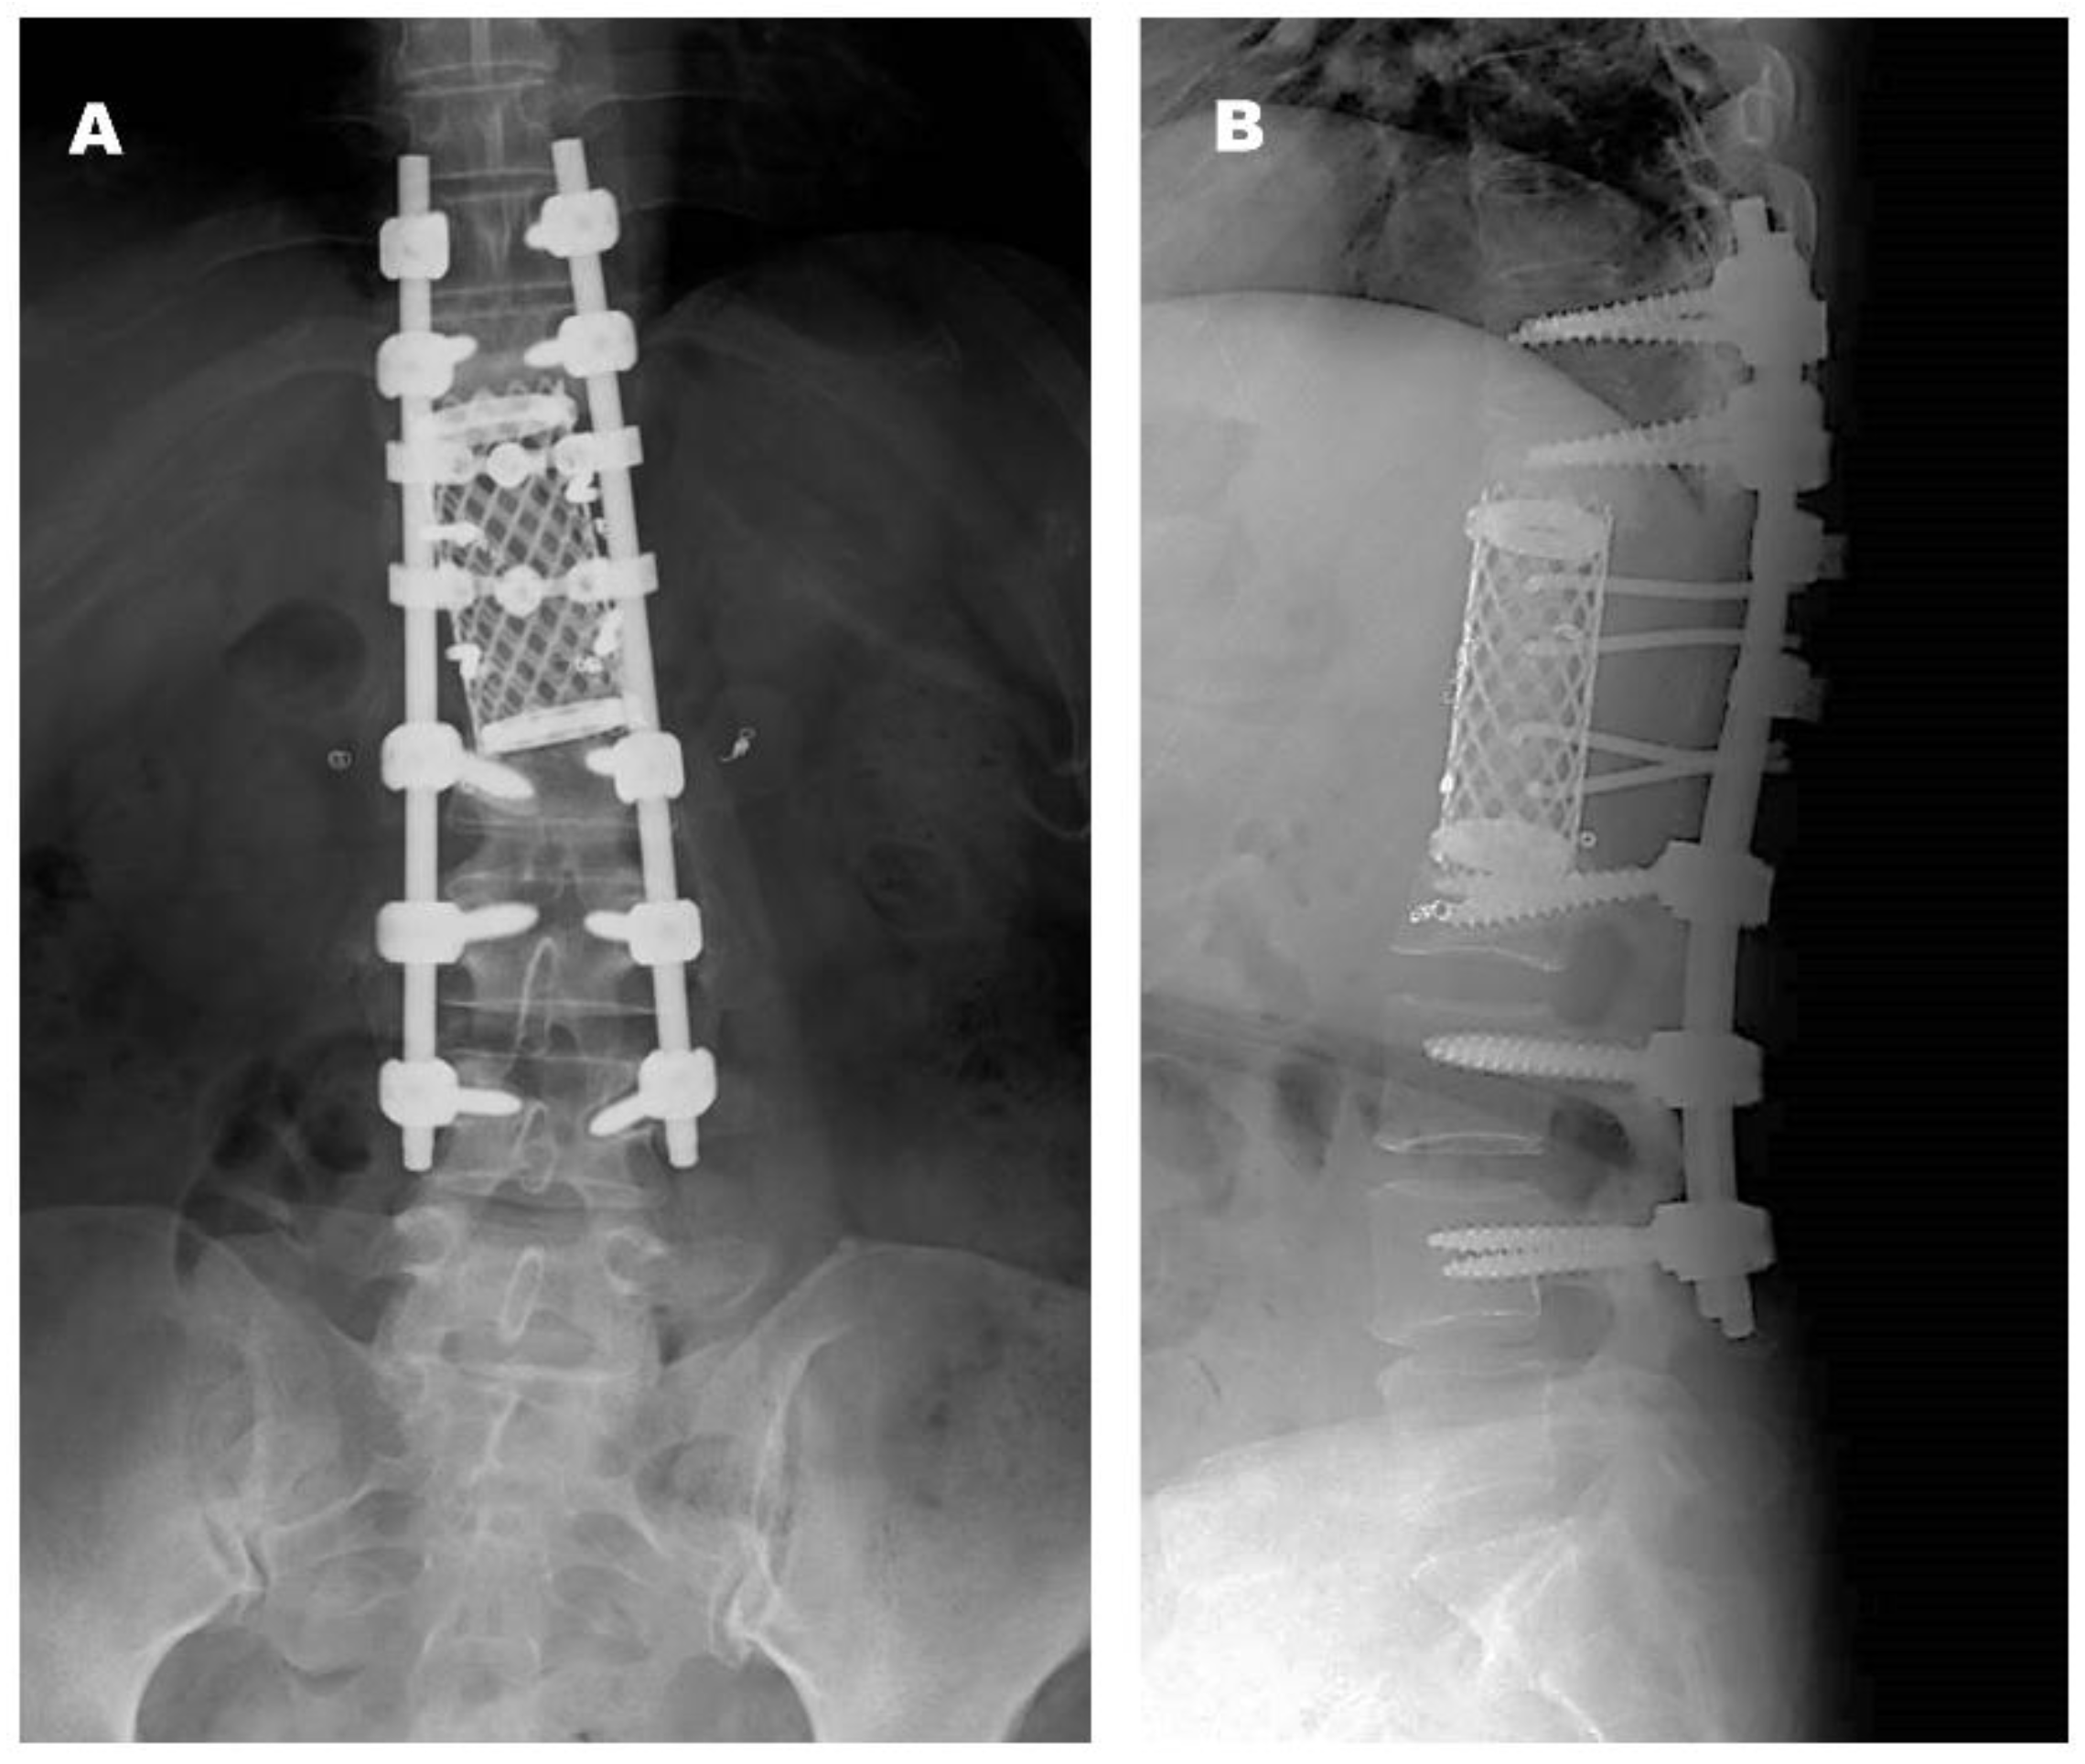

2.1. Case 1

2.2. Case 2